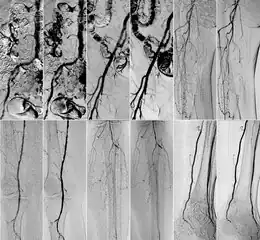

In 2018 Gyánó M. et al. compared the quality of DVA and DSA (digital subtraction angiography) images in a prospective observational crossover study, which involved the analysis of 232 image pairs of 42 patients undergoing lower limb x-ray angiography (performed by using iodinated contrast agent) between February and June 2017. Methods included the measurement of SNR (signal-to-noise ratio) and visual quality comparison.[1]

Qualitative comparison has been performed by three vascular surgeons and three interventional radiologists, with about 17 years of experience on the average. In an online visual questionnaire, which showed DVA and DSA image pairs of the same anatomical regions, raters were asked to choose the image which they found to be more useful for making the diagnosis. Overall, the raters judged the kinetic images better in 69% of all images. Regarding different anatomical regions, the raters agreed that the DVA was significantly better for talocrural and popliteal regions.